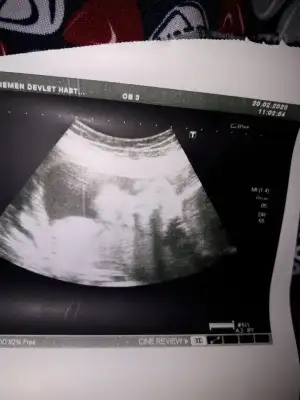

Arkadaşlar 10haftalik acama kizami erkek mi çok penziyo merak ediyorum

Eklentiler

• 15832202238201395352965.webp

15832202238201395352965.webp

29,1 KB · Görüntüleme: 288